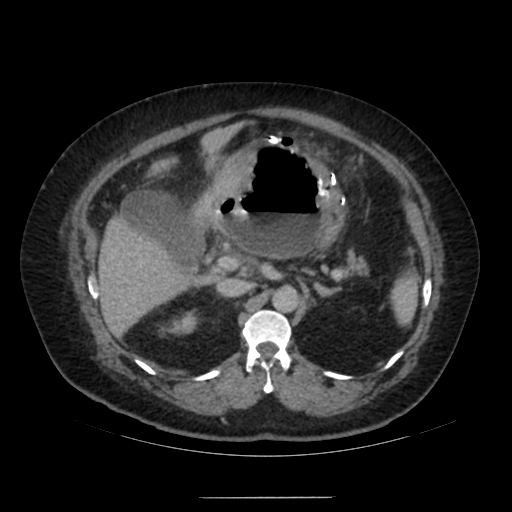

수술 후 복강 내 상태를 확인하기 위해 복부 CT를 촬영함.

복부 CT를 보면 수술부위 쪽으로 아주 큰 pocket이 형성되고 그 안쪽에 air-fluid level이 형성되어 있는 것을 확인할 수 있음.

해당 부분은 수술로 문합을 한 GE junction 쪽으로 염증의 위치로 생각할 수 있음.

추후 외과 과장님께 들어보니 sleeve op. 이후 leakage가 주로 생기는 위치는 gastro-esophageal junction 쪽이며, 천장으로는 liver(간), 좌측으론 spleen과 omentum이 있어 주변으로 염증이 퍼지지 않고 위 사진처럼 갇힌 형태의 염증이 생성된다고 한다.

1. About 14cm sized air-containing complicated fluid collection around the stomach.

: probable leakage at sleeve gastrectomy site.